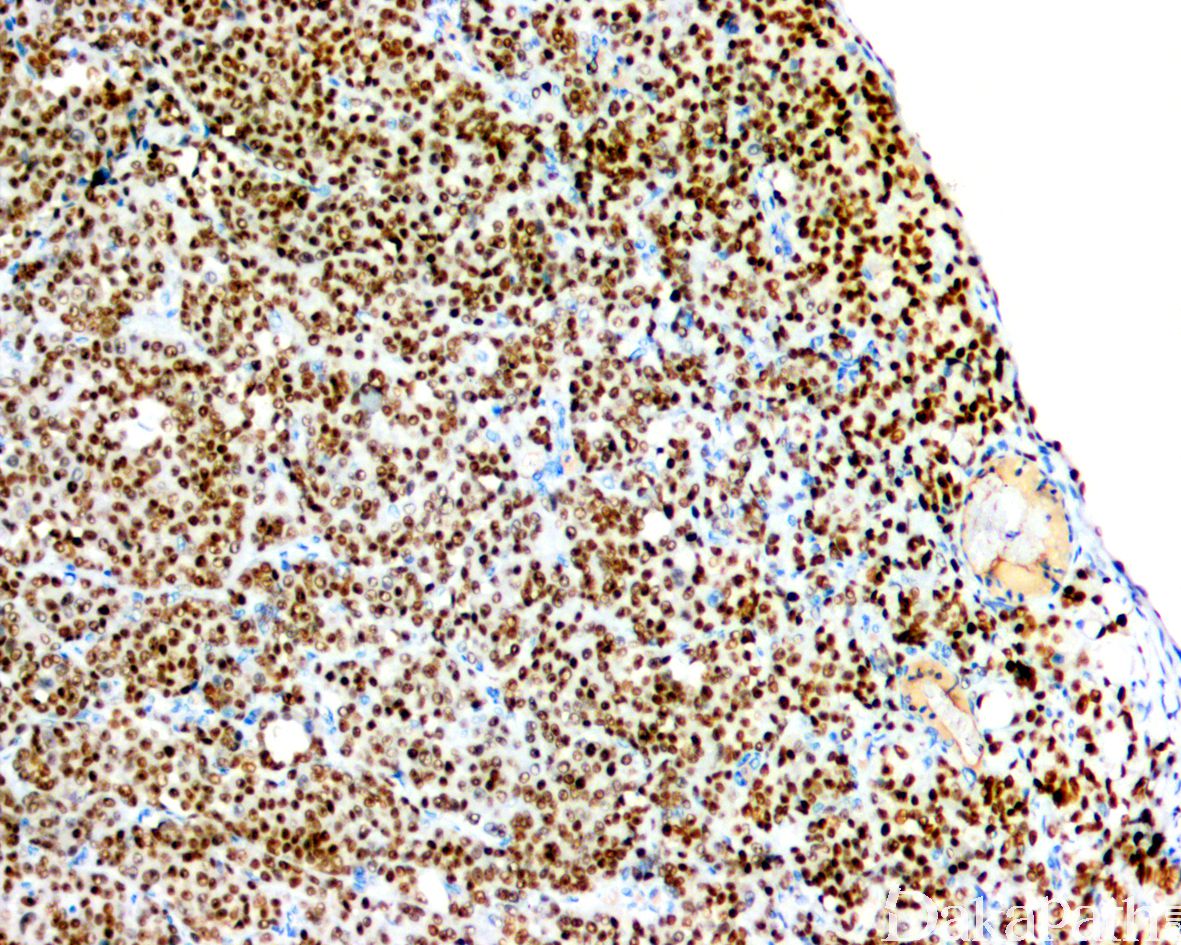

免疫组织化学染色:

浆细胞样尿路上皮癌与普通的尿路上皮癌具有相似的免疫表型特征表达 GATA3(80%),P63(45%),CK7( 92%),CK20(70%)。由于 CDH1 基因突变,浆细胞样尿路上皮癌常出现 E-cadherin 表达缺失。少数可表达 GCDFP15,PR,CDX2 等。部分可表达 CD128,需要与浆细胞瘤鉴别,但不表达 CD38 和 MUM1 等浆细胞标志物。

CDH1 基因体细胞突变,导致 E-cadherin 表达缺失